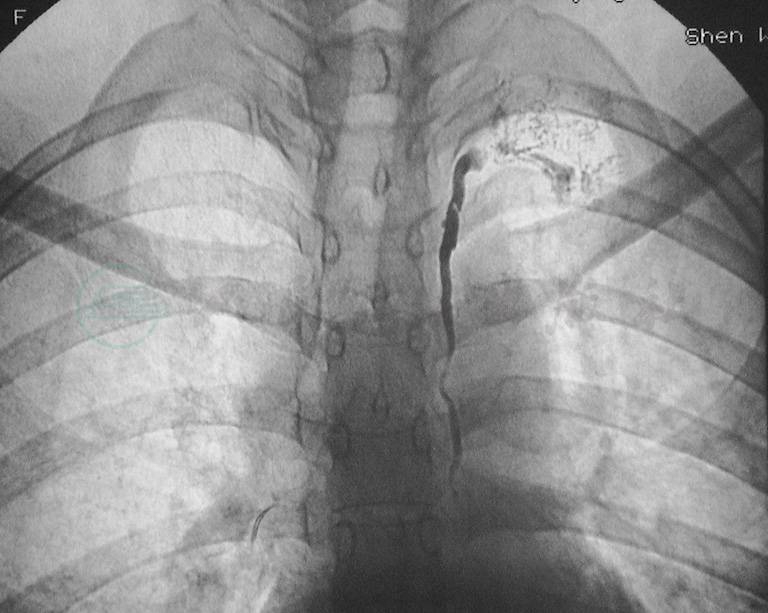

我组乳糜性腹水病例中,有一对来自吉林的母子同患乳糜性腹水,影像学均表现为原发性腹膜后淋巴管发育不全。儿子同时有乳糜性胸水和下肢淋巴水肿(图1)。

图1母子同患乳糜胸腹水

母亲45岁,A.核素淋巴显像:腹股沟淋巴结核素浓聚,腰淋巴干未显影。儿子18岁,伴有右下肢淋巴水肿,经右足背直接淋巴管造影显示:B.右下肢淋巴水肿,小腿淋巴管网状扩张;C.腹膜后淋巴管发育不全,右腹股沟有淋巴管侧支代偿形成;D.经右耳后淋巴管直接淋巴管造影显示:颈干形成不全,未汇入颈静脉角区域,并向颈前反流。母亲保守治疗腹水消失,儿子行腹腔静脉转流术良好控制